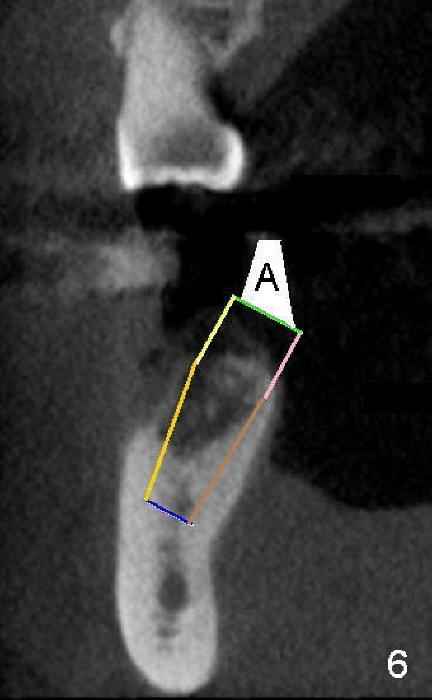

五十多岁的吴先生右下六有根分叉感染(图一),有一次到外地出差疼痛难忍拔除了,一两年后才同意植牙,图二显示已经愈合近远中(M, D)牙槽窝,六乘十七毫米植牙(图三I)好像种得很端正,其实并不完全是这样。让我们回到图二,沿着虚线做个冠状切面,显示右上六号牙以及右下六牙槽骨(图四*),与对侧六号牙冠状切面(图五)对比,右下六牙槽骨往舌侧(L)倾斜(B:颊侧),要植入长而宽的植牙,它就往舌侧倾斜(图八)。为了与对侧牙齿咬合,必须用二十度倾斜的基牙(图六A),但是临床上通过基牙而改变的角度还不够(图七),所以最后牙冠(图十C)不在植牙(I)长轴上,也就是一部分牙冠是悬臂的(*),容易造成陶瓷断裂,基牙松动。避免悬臂牙冠最好的方法便是拔牙后即刻植牙(图九),如果骨质已经吸收,植骨(图十一红色)或者骨扩张时尽量让颊侧骨板往颊侧移动,纠正植牙倾斜角度。